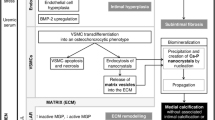

Cholesterol embolization requires the presence of a cholesterol-rich atheromatous plaque in a proximal vessel. Following an inciting event, or spontaneously, as was more common when first reported, the plaque erodes and exposes the underlying lipid-rich core, composed of calcium, lipids including cholesterol crystals, smooth muscle, platelets, fibrin, and mononuclear cells. The plaque debris embolizes to small-to-medium-dimensional vessels, resulting in local occlusion of blood flow. The presence of these emboli triggers a foreign body response, resulting in local acute inflammatory response at sites of said showers of emboli. The inflammatory infiltrate includes neutrophils and eosinophils in the walls of the involved vessels, resulting in local thrombus formation and occlusion of blood flow.

For the confirmation of the diagnosis, biopsy of the skin lesion or involved organ may be required. Typically this means a skin, kidney, or muscle biopsy. Skin biopsy is considered the safest and highest-yielding choice when skin lesions are noted. Cholesterol emboli appear as elongated, biconvex, needle-shaped clefts in the vessels with inflammation surrounding the involved vessel in all involved organs (Fig. 16.1). Arteriosclerotic lesions and hyalinosis of the glomeruli or tubules can be noted, especially in the setting of ischemic nephropathy from repeated embolic showers. Renal parenchyma might show wedge-shaped infarcts in the cortical areas in areas involved by obstructed vessels (Fig. 16.2).